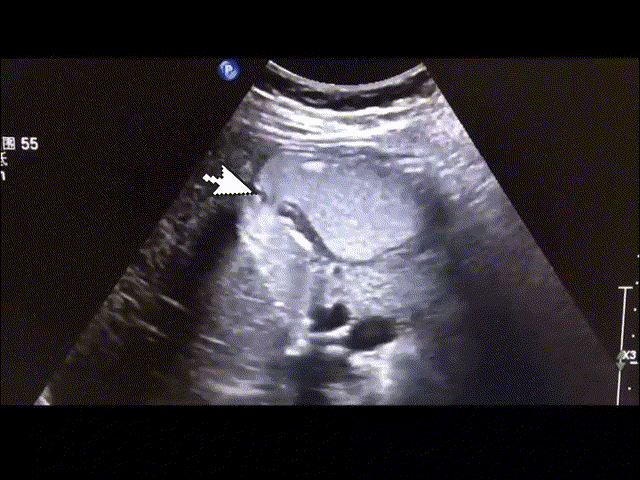

40岁的李女士上腹饱胀不舒服两个多月。曾经做胃镜检查,未发现明显病变。来到第二人民医院超声科,进行胃充盈超声检查。在超声动态观察下,发现李女士存在胃十二指肠幽门反流情况。于是进行对症治疗,两周后症状明显好转。

胃造影用的是什么机子胃肠超声造影--无创、无痛、无辐射!_https://www.jmylbn.com_新闻资讯_第20张

十二指肠幽门反流图